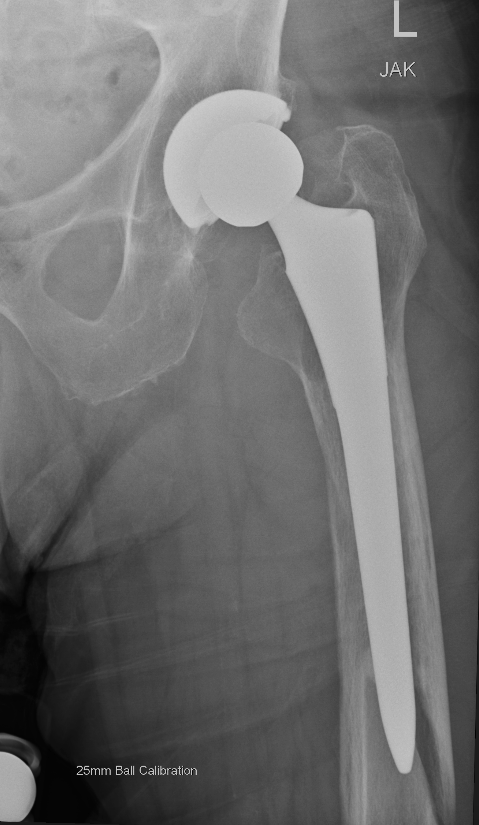

Long stem uncemented revision with cortical strut allograft

Long stem uncemented revision with plate + cortical struts